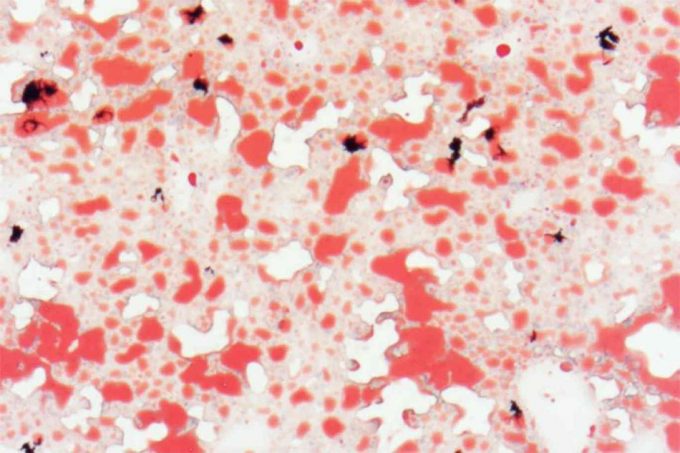

En la investigación, los expertos utilizaron la trehalosa en el agua potable que tomaban los roedores del estudio, para comprobar qué genes se activaban en el hígado de los animales tras su ingesta. Además de la identificación del gen Aloxe3, se constató que los roedores experimentaron los efectos positivos antes comentados, similares a los obtenidos en otra prueba en la que se proporcionó a los ratones agua sin el disacárido durante un periodo de dos días de ayuno, descubriendo que el ayuno tenía el mismo efecto.